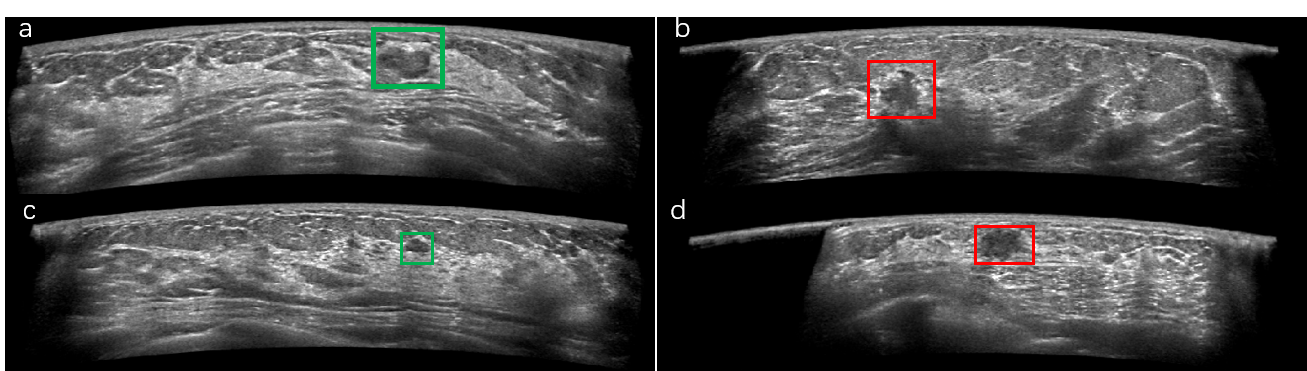

Refer to caption

Figure 1: Example ABUS images, the area in the box is the lesion marked by the doctor, where a, c are benign lesions, and b, d are malignant tumors.

Nevertheless, developing computer-aided diagnosis (CAD) schemes for ABUS images remains challenging. As shown in Fig. 1, 1) compared with other imaging modality, ultrasound imaging quality is relatively poor, thus making the boundary labeling difficult; 2) in most cases the proportion of lesion areas is less than 1%, at the same time, the high similarity of benign and malignant lesions makes the classification task difficult; 3) the reconstructed ABUS images have approximately 800 frames, which requires huge computing resources.